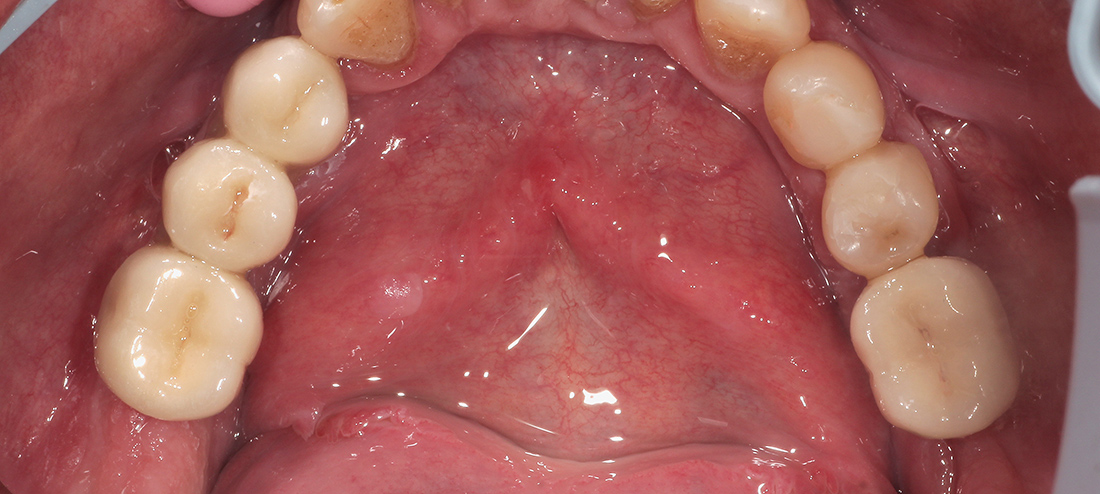

Вторым этапом были удалены боковые зубы нижней челюсти, также с одномоментной имплантацией и пластикой тканей. Период интеграции имплантов протекал без особенностей и через четыре месяца после начала лечения мы перешли к окончательному протезированию.

Окончательное протезирование было выполнено тремя металлокерамическими мостовидными конструкциями на верхней челюсти, мостовидным протезом внизу справа и отдельной коронкой на импланте в области шестого зуба нижней челюсти слева. Фиксация коронок проводилась на индивидуальные циркониевые абатмены одноэтапно.